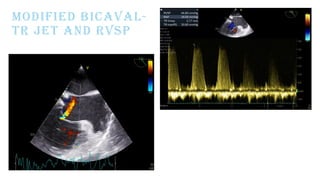

MODIFIED BICAVAL-

TR JET AND RVSP

PRE CPB TEE

oFair LVSF; EF - 30%, CO - 2.8L/m, CI - 1.4L/min/m2

oFair RVSF; RVEF - 26%, RVFAC - 24%, TAPSE – 11 mm

oApical VSR+,

oIt is a complex VSR at the apical ventricular septal level showing

multiple jets across the thin apical septum.

oQp/Qs=2.0

oRWMA+; Apex thinned out. Akinesia of mid mid-anterior and inferior

wall

oMild TR; Mild PAH (RVSP=46)

oMild MR